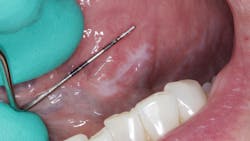

During her routine oral screening and exam, a 9 mm x 3 mm white leukoplakic patch of tissue on the left ventral surface of the tongue was noted. It was not tender to palpation, could not be scraped off, and the patient was unaware of its presence. It was recommended that the patient come back in two to three weeks to assess for continued presence.

The patient was referred to an oral surgeon where evaluation and an excisional biopsy were performed.

Definitive diagnosis: Keratosis with lichenoid chronic inflammation